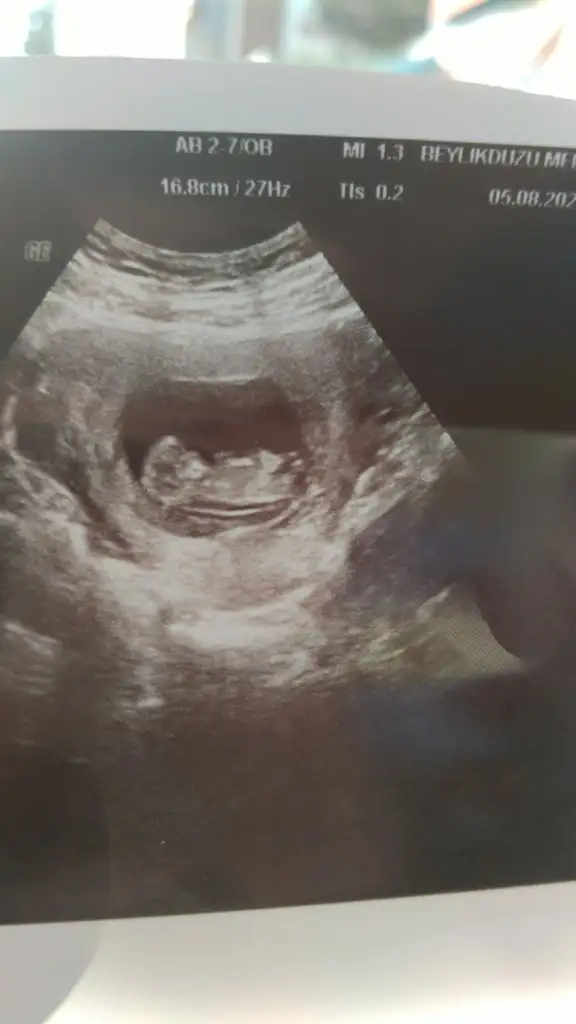

Eki Görüntüle 3282717